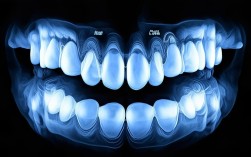

- 复杂病因: 牙齿不齐的原因多种多样(遗传、不良习惯、牙周病、颌骨发育问题等),只有通过专业检查(包括口腔检查、X光片、头影测量、模型分析等),医生才能准确判断病因、牙齿移动的潜力、颌骨关系以及是否存在潜在风险(如牙根吸收、颞下颌关节问题)。

- 全面评估: 医生会进行详细的口腔检查、拍摄X光片(如全景片、头颅侧位片)、取牙齿模型等,全面评估你的口腔状况、牙齿问题、骨骼关系和矫正潜力。